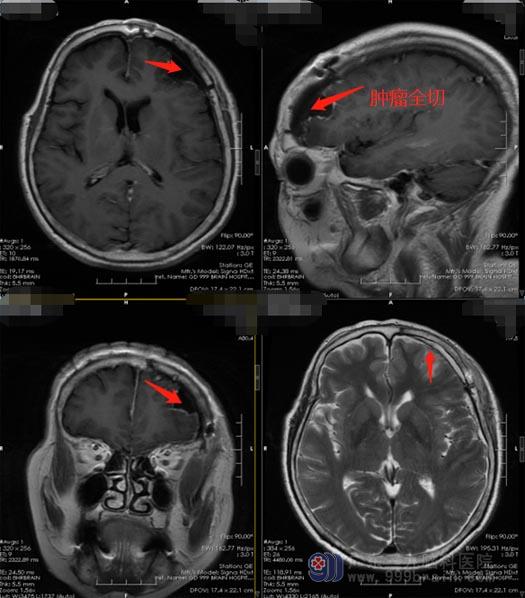

详细地讲解病情后,邹奶奶及家属都积极地配合治疗,由医院副院长、神经外五科主任鲁明主刀在全麻下行左侧额部占位性病变切除术,术后病理结果证实:(左侧额部)纤维型脑膜瘤,WHO1级。经过术后一周多的康复治疗,邹阿姨已满意出院了。